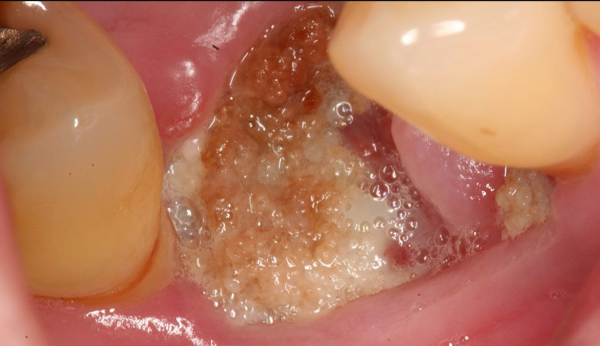

Những triệu chứng trên có thể là dấu hiệu của nhiễm trùng, áp-xe, hoặc viêm xương ổ răng – các biến chứng nghiêm trọng cần được bác sĩ xử lý kịp thời.

Ngoài ra, tái khám định kỳ theo chỉ định sẽ giúp bác sĩ theo dõi tiến trình lành thương, phát hiện sớm các bất thường và đảm bảo hiệu quả điều trị được duy trì lâu dài.